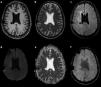

The follow-up brain MRI scan performed in 2017 detected a new cystic lesion in the right corona radiata, which displayed progressive growth in subsequent studies (Fig. 1). Clinical examination identified no new neurological alterations or deficits. The lesion was cystic and septated, isointense to CSF on all sequences, was not surrounded by oedema or gliosis, and presented no diffusion restriction or contrast enhancement. It was located in the radiation field and surrounded by multiple punctiform haemorrhagic foci, visible on magnetic susceptibility sequences, in the adjacent white matter (Fig. 2).8

Status of the lesion in an MRI study performed in 2020. a) Non-contrast T1-weighted 3D-SPGR sequence; b) T2-weighted TSE sequence; c) 3D T2-FLAIR sequence; d) diffusion sequence (b = 1000); e) ADC map; f) magnetic susceptibility sequence. The lesion is isointense to CSF on T1- and T2-weighted sequences (a, b), and presents signal suppression on T2-FLAIR sequences (c), which suggests free water in the centre and absence of peripheral oedema or gliosis; it also presents facilitated diffusion (d, e). The magnetic susceptibility sequence shows hypointense haemorrhagic foci near the lesion, within the radiation field (f).